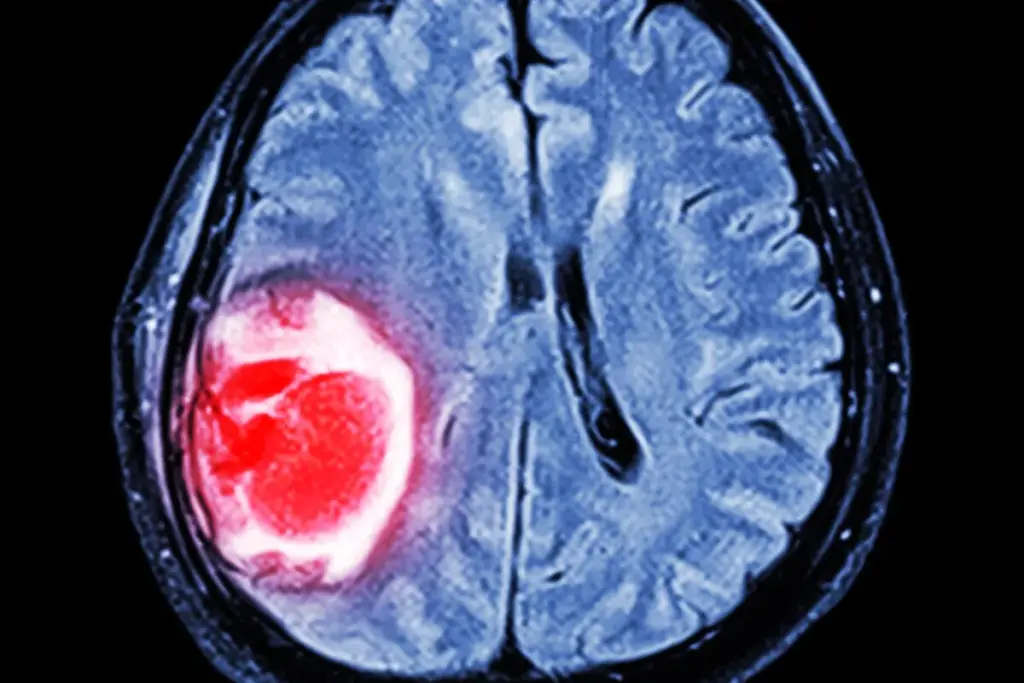

Imaging Tests (MRI, CT, PET)

Imaging tests are vital for finding brain tumors. We use different tests to get different views of the tumor.

- MRI (Magnetic Resonance Imaging): MRI shows soft tissue details well. It helps find where the tumor is, how big it is, and how it’s related to other parts of the brain.

- CT (Computed Tomography): CT scans are fast and good for emergencies. They show if there’s a tumor, how big it is, and if there’s bleeding or calcium.

- PET (Positron Emission Tomography): PET scans check how active the tumor is. This helps tell what kind of tumor it is and how serious it is.